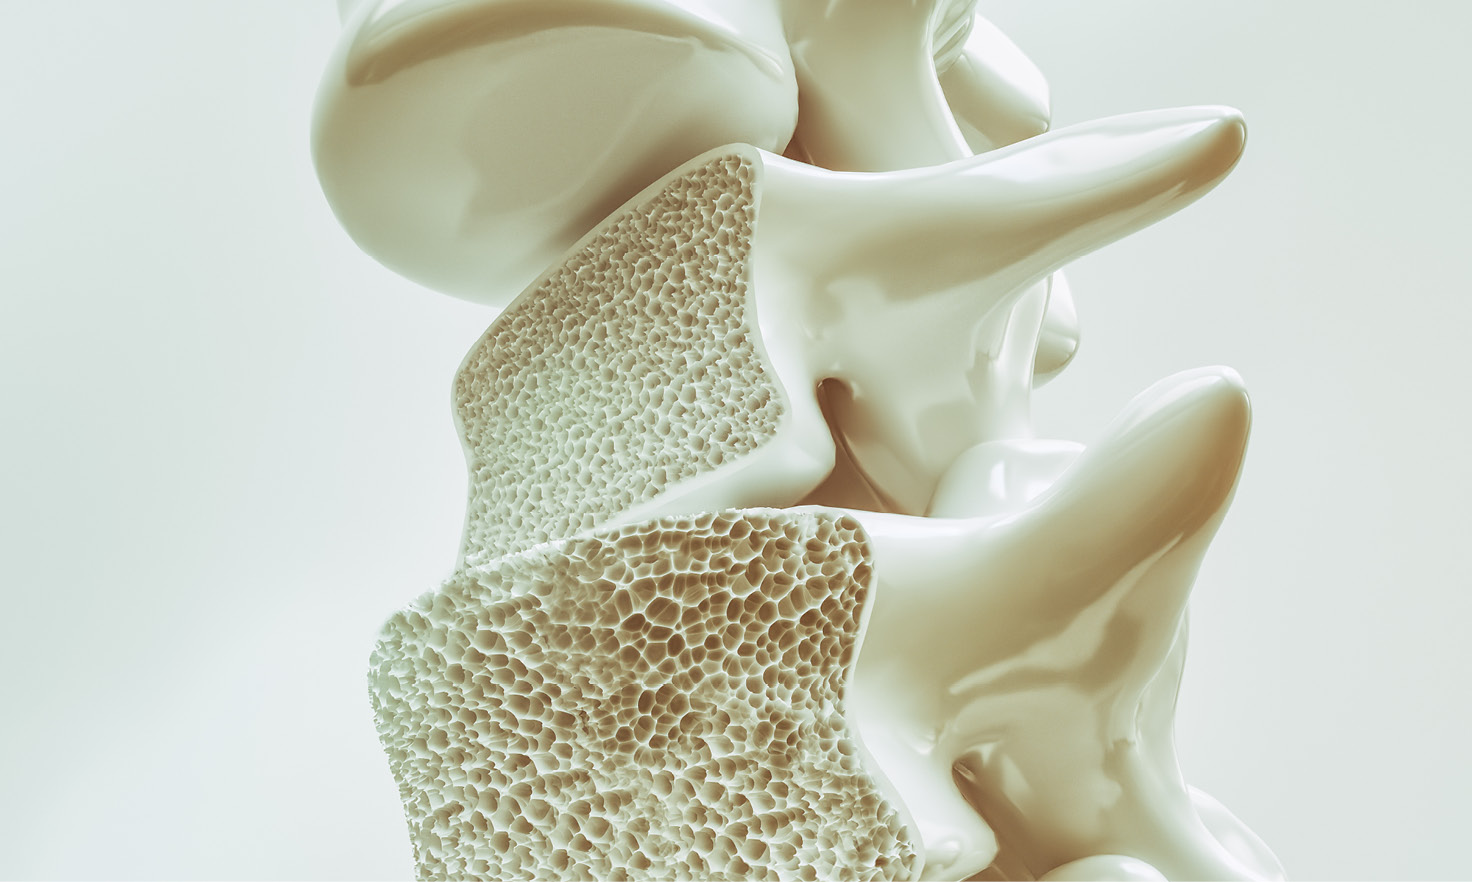

هل تعلم أن عظامنا هي الأنسجة الحية؟ للحفاظ على قوتها، تحطم أجسامنا العظام القديمة وتستبدلها بعظام جديدة. عندما نكون صغارًا، نبني عظامًا أكثر مما ننهار. ولكن مع تقدمنا في السن، يمكن أن تنهار العظام في كثير من الأحيان أكثر مما يتم استبداله. هذا يمكن أن يؤدي إلى هشاشة العظام.

يمكن أن يتطور هشاشة العظام إذا انخفضت كتلة العظم أو تغيرت بنية عظامك. هشاشة العظام تجعل عظامك ضعيفة ومن المرجح أن تتعرض للكسر.

يُطلق على هشاشة العظام مرضًا “صامتًا” لأنه لا يظهر أي أعراض واضحة. كثير من الناس لا يعرفون أنهم مصابون به حتى يكسروا عظمًا بعد إصابة طفيفة أو حركة. شيء بسيط مثل السقوط من ارتفاع الوقوف أو الانحناء أو الرفع أو حتى السعال المكثف قد يسبب كسرًا. يمكن أن يتطور مرض هشاشة العظام في أي عظم، لكنه أكثر شيوعًا في عظام الوركين والمعصمين والفقرات في العمود الفقري.